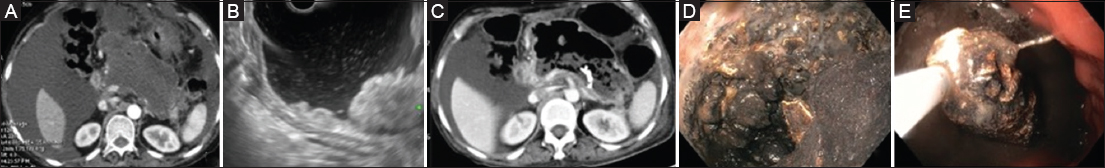

The procedure was technically successful in all patients in both groups (Fig. 2,3), whereas clinical success was significantly higher in the LAMS group: 40 (89%) patients vs. 10 (48%) patients; P<0.001. All patients in the LAMS group underwent stent removal within 6 weeks of placement, as per protocol. In the LAMS group, 5 patients required rescue surgery because of bleeding accompanied by ongoing sepsis (during necrosectomy in 3 patients and post necrosectomy in 2 patients) and persistent necrotic collection, whereas 11 (52%) patients in the MPS group required rescue surgery (bleeding resulting in hemodynamic compromise in 5 patients, during necrosectomy in 4 patients and post necrosectomy in 1 patient, and ongoing sepsis with persistent necrotic collection in 6 patients). ETN was performed more frequently in the MPS group than in the LAMS group: 18 (86%) patients vs. 26 (58%) patients, respectively; P=0.02. Patients with MPS required more necrosectomy sessions to achieve a successful outcome compared to those with LAMS (6.1±1.9 vs. 4.1±1.1; P=0.009). Additional percutaneous drainage was needed more frequently in the MPS group than in the LAMS group: 10 (47.1%) vs. 6 (13%), respectively; P=0.004. Patients in the LAMS group required fewer days for resolution compared to the MPS group: mean of 22 days vs. 34 days; P<0.001. Four (19%) patients in the MPS group succumbed to their illness as compared to 3 (6%) patients in the LAMS group (P=0.19).

thumblarge

Figure 2 (A) An ill-defined necrotic collection (day 23 or illness). (B) EUS showing solid necrotic debris. (C) CT 3 days after transmural plastic stent placement: liquid content drained out with solid. Necrotic content remaining. (D) Endoscope taken into the cavity after dilation of the transmural tract: significant solid debris present. (E) DEN being performed EUS, endoscopic ultrasound; CT, computed tomography; DEN, direct endoscopic necrosectomy